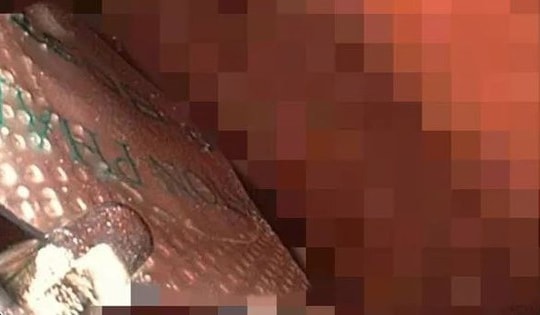

Sau gần một giờ phẫu thuật, các bác sĩ đã lấy thành công cả hai chiếc thìa ra khỏi bụng người đàn ông.